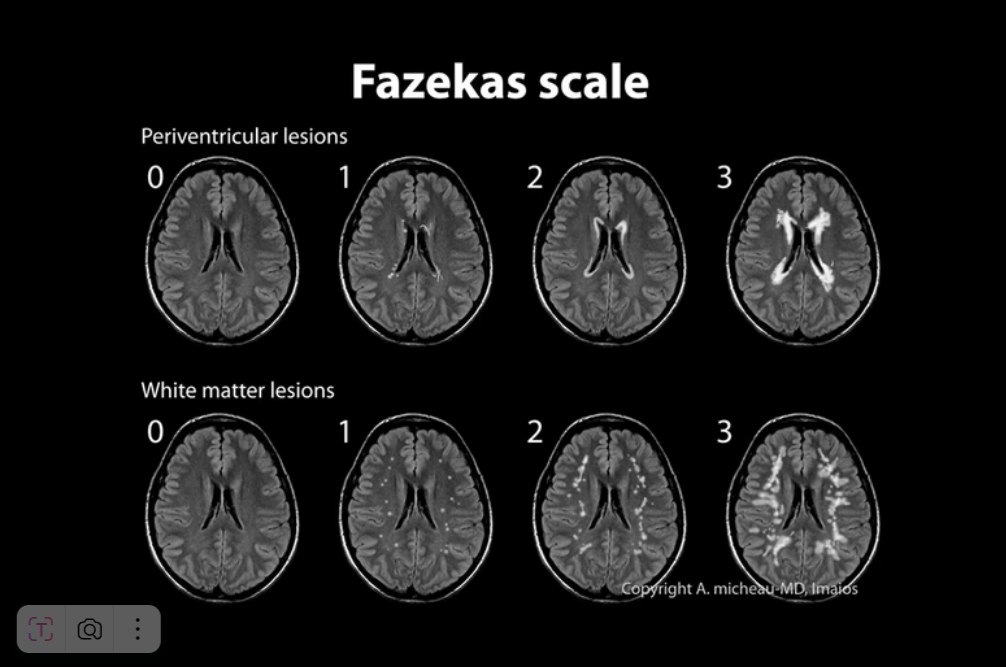

Fazekas grades

Fazekas grades. Шкала Фазекас мрт. Fazekas классификация мрт. Фазекас 2. 3 Ст. по Fazekas.

Fazekas grades. Фазекас классификация мрт. Очаги Фазекас мрт. Шкала Фазекас мрт. Церебральная микроангиопатия головного мозга Fazekas 2 степени.

Fazekas grades. Фазекас классификация мрт. Очаги Фазекас мрт. Шкала Фазекас мрт. Церебральная микроангиопатия головного мозга Fazekas 2 степени.

Fazekas grades. Лейкоареоз Фазекас. Fazekas 0. Фазекас 3. Фазекас классификация мрт.

Fazekas grades. Лейкоареоз Фазекас. Fazekas 0. Фазекас 3. Фазекас классификация мрт.

Fazekas grades. Fazekas степени мрт. Фазекас 2 мрт. Шкала Фазекас мрт. Лейкоареоз 3 степени по Fazekas.

Fazekas grades. Fazekas степени мрт. Фазекас 2 мрт. Шкала Фазекас мрт. Лейкоареоз 3 степени по Fazekas.

Fazekas grades. Классификация Фазекас. Fazekas мрт. Лейкоареоз степени по Fazekas. Фазекас классификация мрт.

Fazekas grades. Классификация Фазекас. Fazekas мрт. Лейкоареоз степени по Fazekas. Фазекас классификация мрт.

Fazekas grades. Фазекас классификация мрт. Лейкоареоз Fazekas 1 что это. Fazekas степени мрт. Лейкоареоз степени по Fazekas.

Fazekas grades. Фазекас классификация мрт. Лейкоареоз Fazekas 1 что это. Fazekas степени мрт. Лейкоареоз степени по Fazekas.

Fazekas grades. Фазекас 2. Fazekas 0. Фазекас 3.

Fazekas grades. Фазекас 2. Fazekas 0. Фазекас 3.